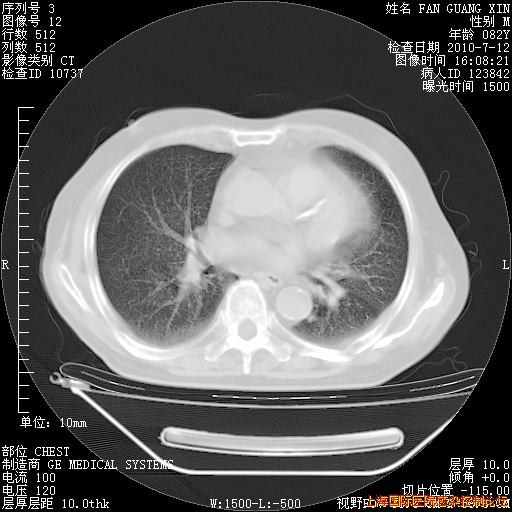

6月12日肺窗

整整相隔30天的肺部CT好像有所好转啊。甲强龙减量第3天,需要观察体温。